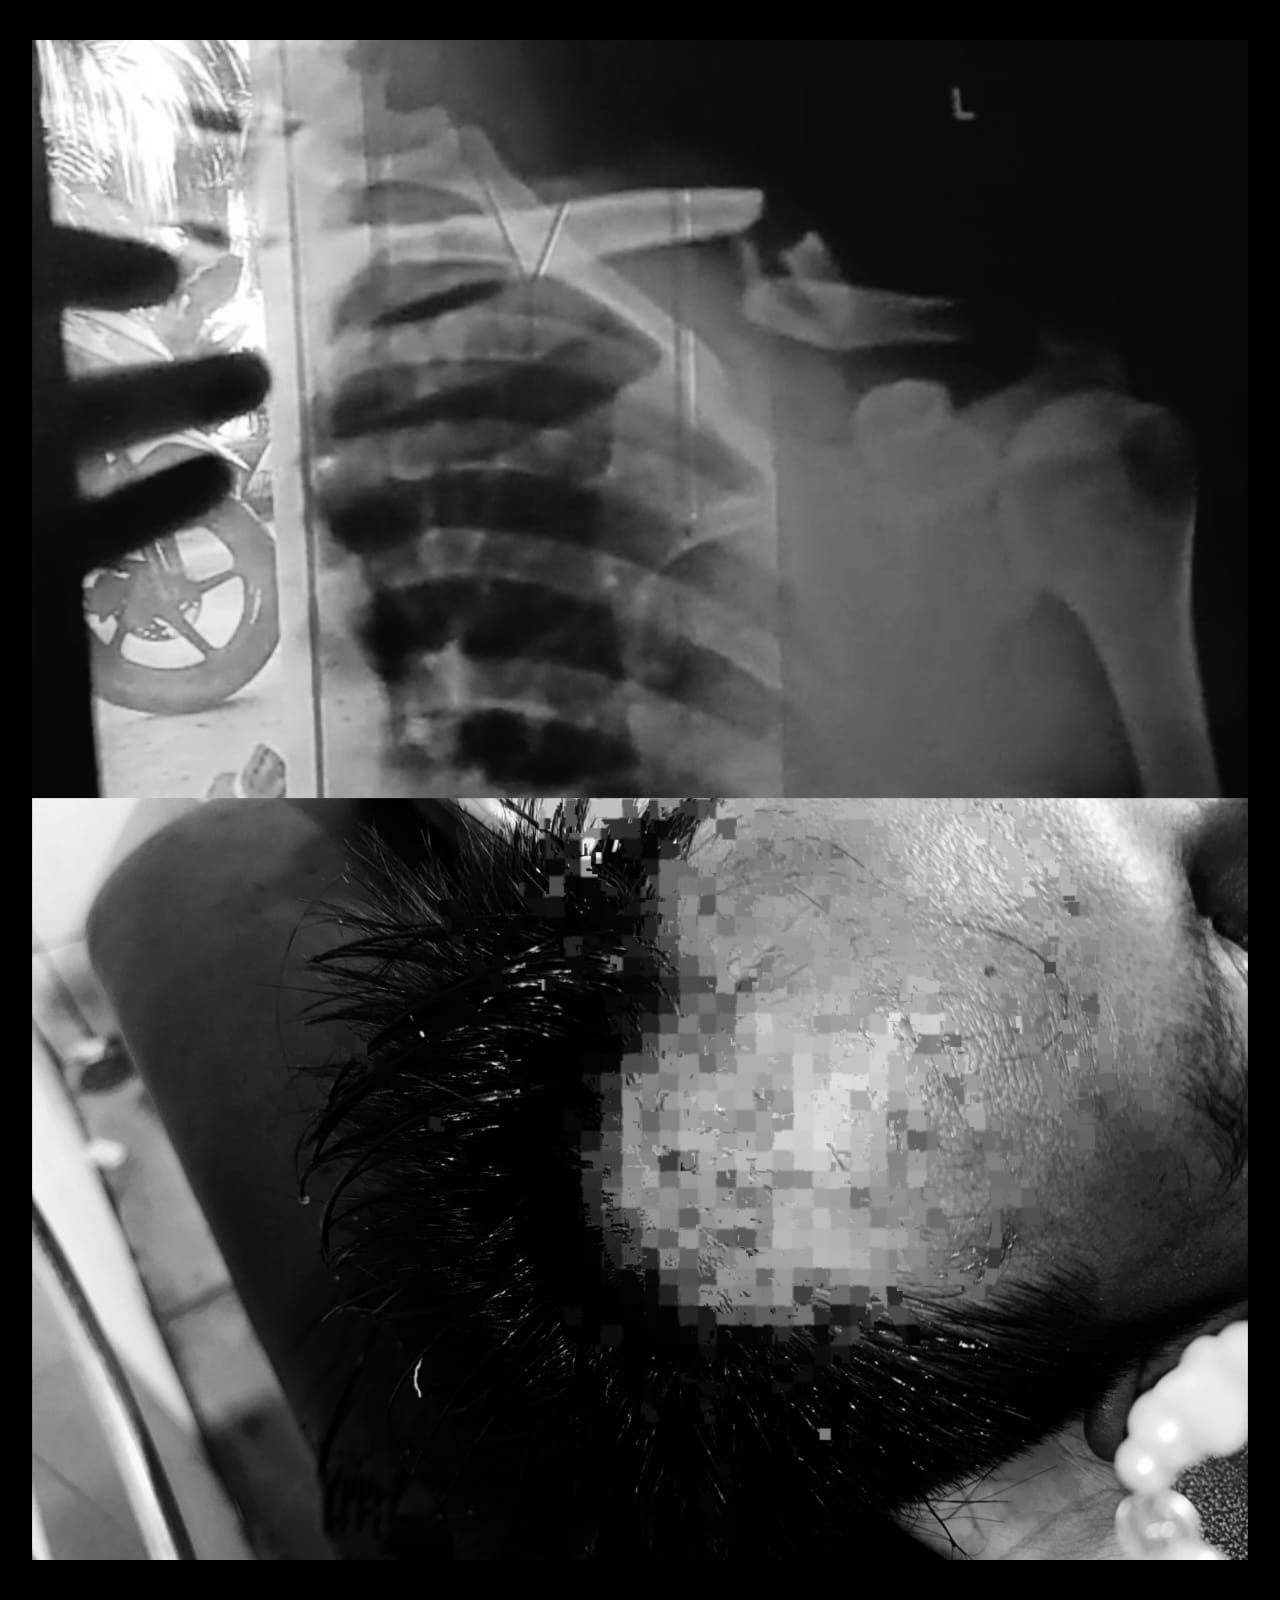

Hasil Rontgen yang melihatkan kondisi korban setelah diserang 10 OTD.--(Sumber Fot: Ahmad/Betv)

Anita mengungkapkan, akibat kejadian tersebut adiknya mengalami sejumlah luka robek hingga patah tulang pada bahu bagian kiri, dan saat ini korban sudah di rawat di rumah.

"Dia sempat kabur dan sembunyi di dalam bilyard, terus pulang ke rumah kondisinya sudah berlumuran darah, dan setelah dibawa kerumah sakit, adik kami mengalami bocor di kepala, luka sobek pada lengan dan kaki hingga tulang bahunya kirinya patah," ungkapnya.